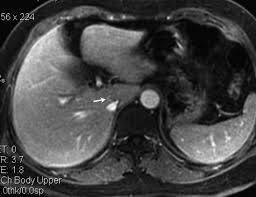

Chiasmata -mə-tə or chiasmas also chiasms 1. Esophageal varices are extremely dilated sub-mucosal veins in the lower third of the esophagus. Located in metro Denver northern Colorado and western Nebraska serving all of the Front Range our team consists of board-certified and fellowship-trained interventional radiologists. This results in hepatic congestion similar to Budd-Chiari syndrome and post-sinusoidal portal hypertension. The patients condition should be monitored throughout the procedure. They are most often a consequence of portal hypertension commonly due to cirrhosis. Toxic injury to liver sinusoids causes sloughing of endothelial cells that embolize to hepatic venules and cause eventual fibrosis of the venules. Coin in the Esophagus. There is no clear consensus regarding the number of occluded veins some authors claim that there should be at least one occluded hepatic vein 7 others state that there are no significant.

Carcinoma of the Colon. Budd-Chiari syndrome a blockage in one or more veins that carry blood from the liver back to the heart. And coumarin skin necrosis adrenal gland hemorrhage and infarction. Toxic injury to liver sinusoids causes sloughing of endothelial cells that embolize to hepatic venules and cause eventual fibrosis of the venules. Chiari malformation CM is a structural defect in the cerebellum characterized by a downward displacement of one or both cerebellar tonsils through the foramen magnum the opening at the base of the skull. Embolism and thrombosis of. La présence dune ou plusieurs affections prothrombotiques est fréquente La prise en charge repose sur un traitement anticoagulant précoce le traitement de l.